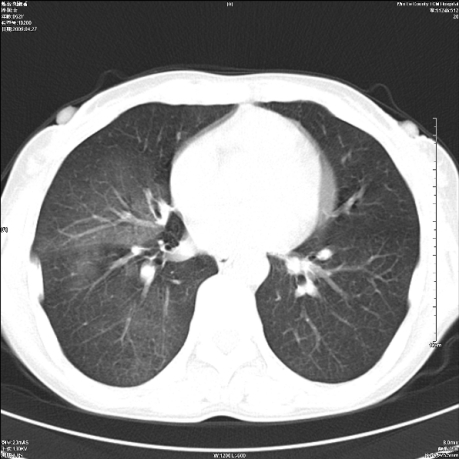

标题: CT19625:女52间断性喀血 [打印本页]

标题: CT19625:女52间断性喀血

考虑右肺下叶支气管病变,tb??

病灶内可见含气影。考虑右肺下叶内基底段炎症

考虑右肺中叶感染性病变并右肺中、下叶肺泡积血;建议抗炎、止血治疗后复查。

右肺中叶炎症;右肺中、下叶肺泡积血

考虑右肺中叶感染性病变并右肺中、下叶肺泡积血。建议治疗后复查。